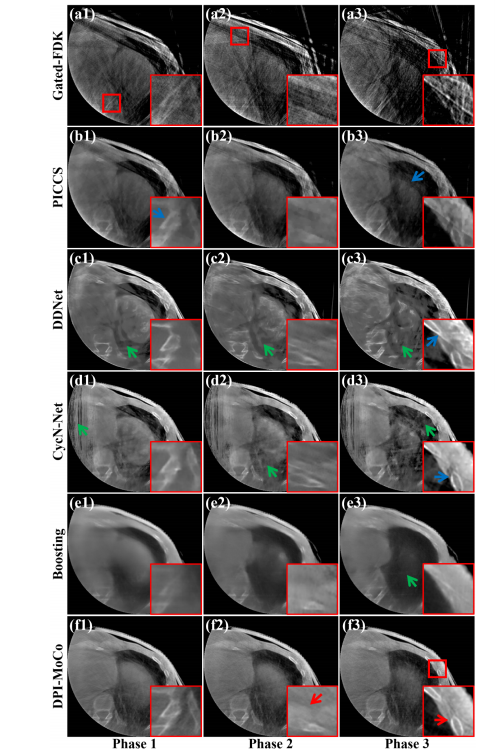

Fig. 4. Reconstructed axial results from three selected phases on the LinaTech dataset for different methods. (a1)-(f1) Reconstructed results at Phase 1, (a2)-(f2) Reconstructed results at Phase 2, (a3)-(f3) Reconstructed results at PhaseThe display window is [0.004, 0.022] mm-1 .

图4. 在LinaTech数据集上,不同方法在三个选定相位的重建轴向结果。(a1)-(f1) 相位1的重建结果,(a2)-(f2) 相位2的重建结果,(a3)-(f3) 相位3的重建结果。显示窗口为 [0.004, 0.022] mm^-1。